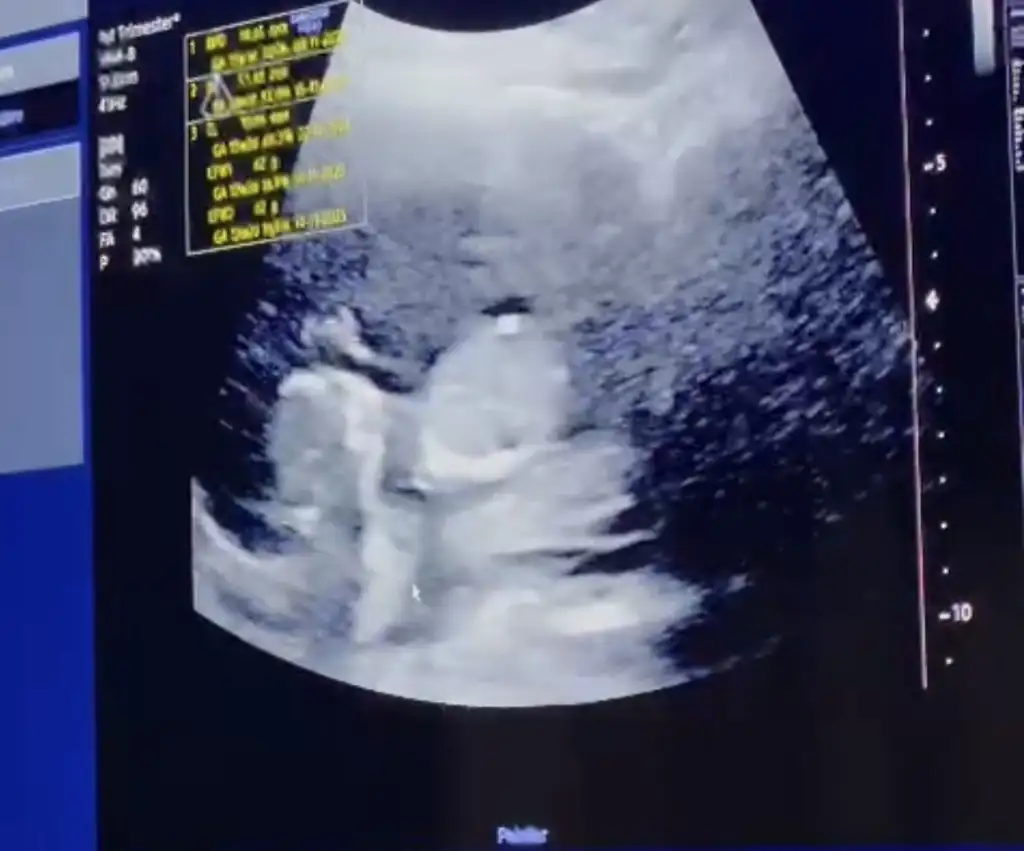

Selam kızlar ben kontrolden geldim her şey yolunda çok şükür burun kemiği ve ense kalınlığı normal yarın nift için kan vercem ☺️ giderken bir kare çikolata yedim beniş o kadar haraketliydi ki o yüzden düzgün bi fotoğrafı yok😂😂 videodan görüntü aldım onu atıyorum. Tahminler kızdı ama doktor bacak arasında çıkıntı gördü resimde okla gösterilen yere bakın 🙈 ilk resimde de eli havada 😍Eki Görüntüle 3242883 Eki Görüntüle 3242884